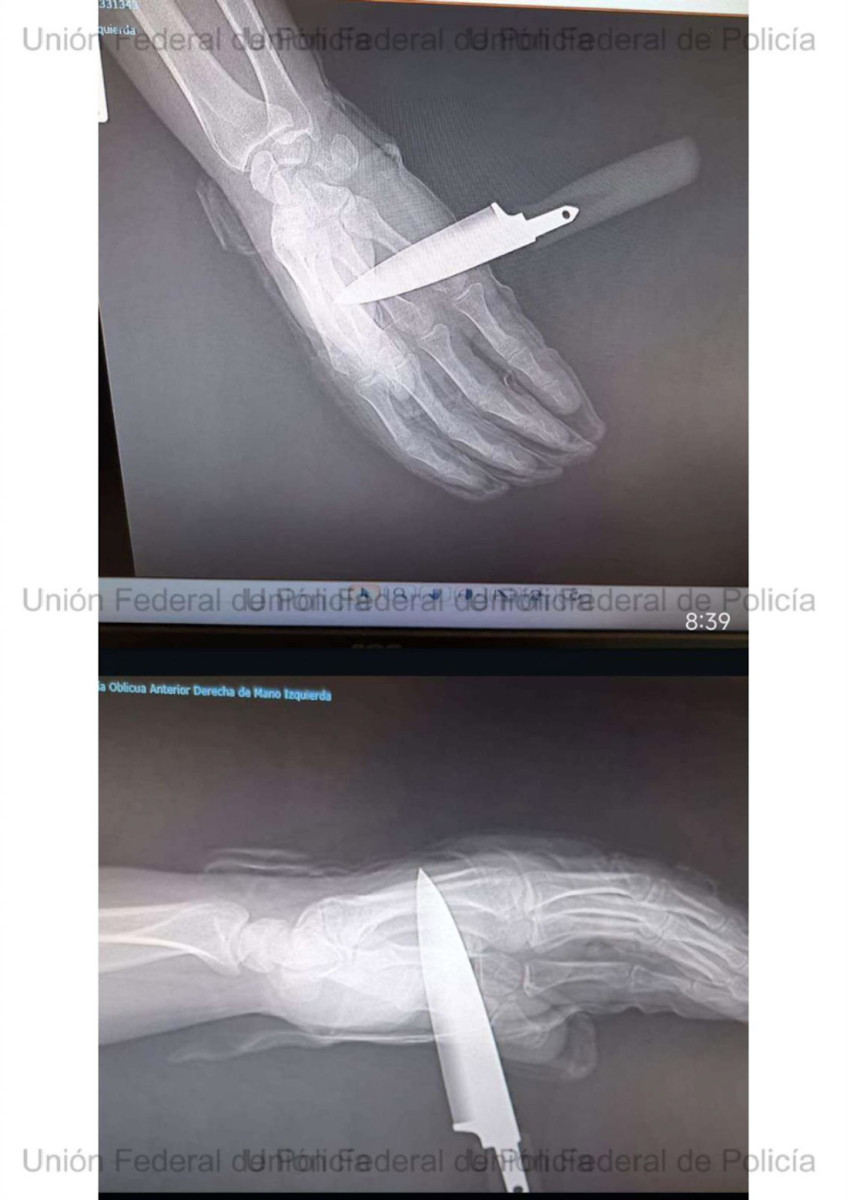

El agente herido tuvo que ser atendido en un centro hospitalario, al que acudió con el cuchillo aún clavado. Desde la UFP han mostrado su “total apoyo” al compañero y han anunciado que solicitarán para él el ingreso en la Orden del Mérito Policial con distintivo rojo en reconocimiento a su actuación.